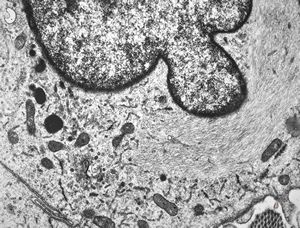

M, 11y. | mycosis fungoides v.s. - cerebriform nucleus of Sézary cell